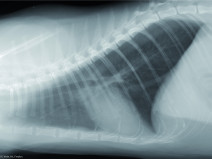

• Soirée TD de radiographie thoracique

Etre capable de :

• décrire les principes à respecter pour obtenir une radiographie thoracique de bonne qualité ;

• adopter une méthodologie pour interpréter des radiographies thoraciques chez les carnivores domestiques.

Le 23 mai 2018

Paris (75008)

Imagerie Médicale

Ile-de-France